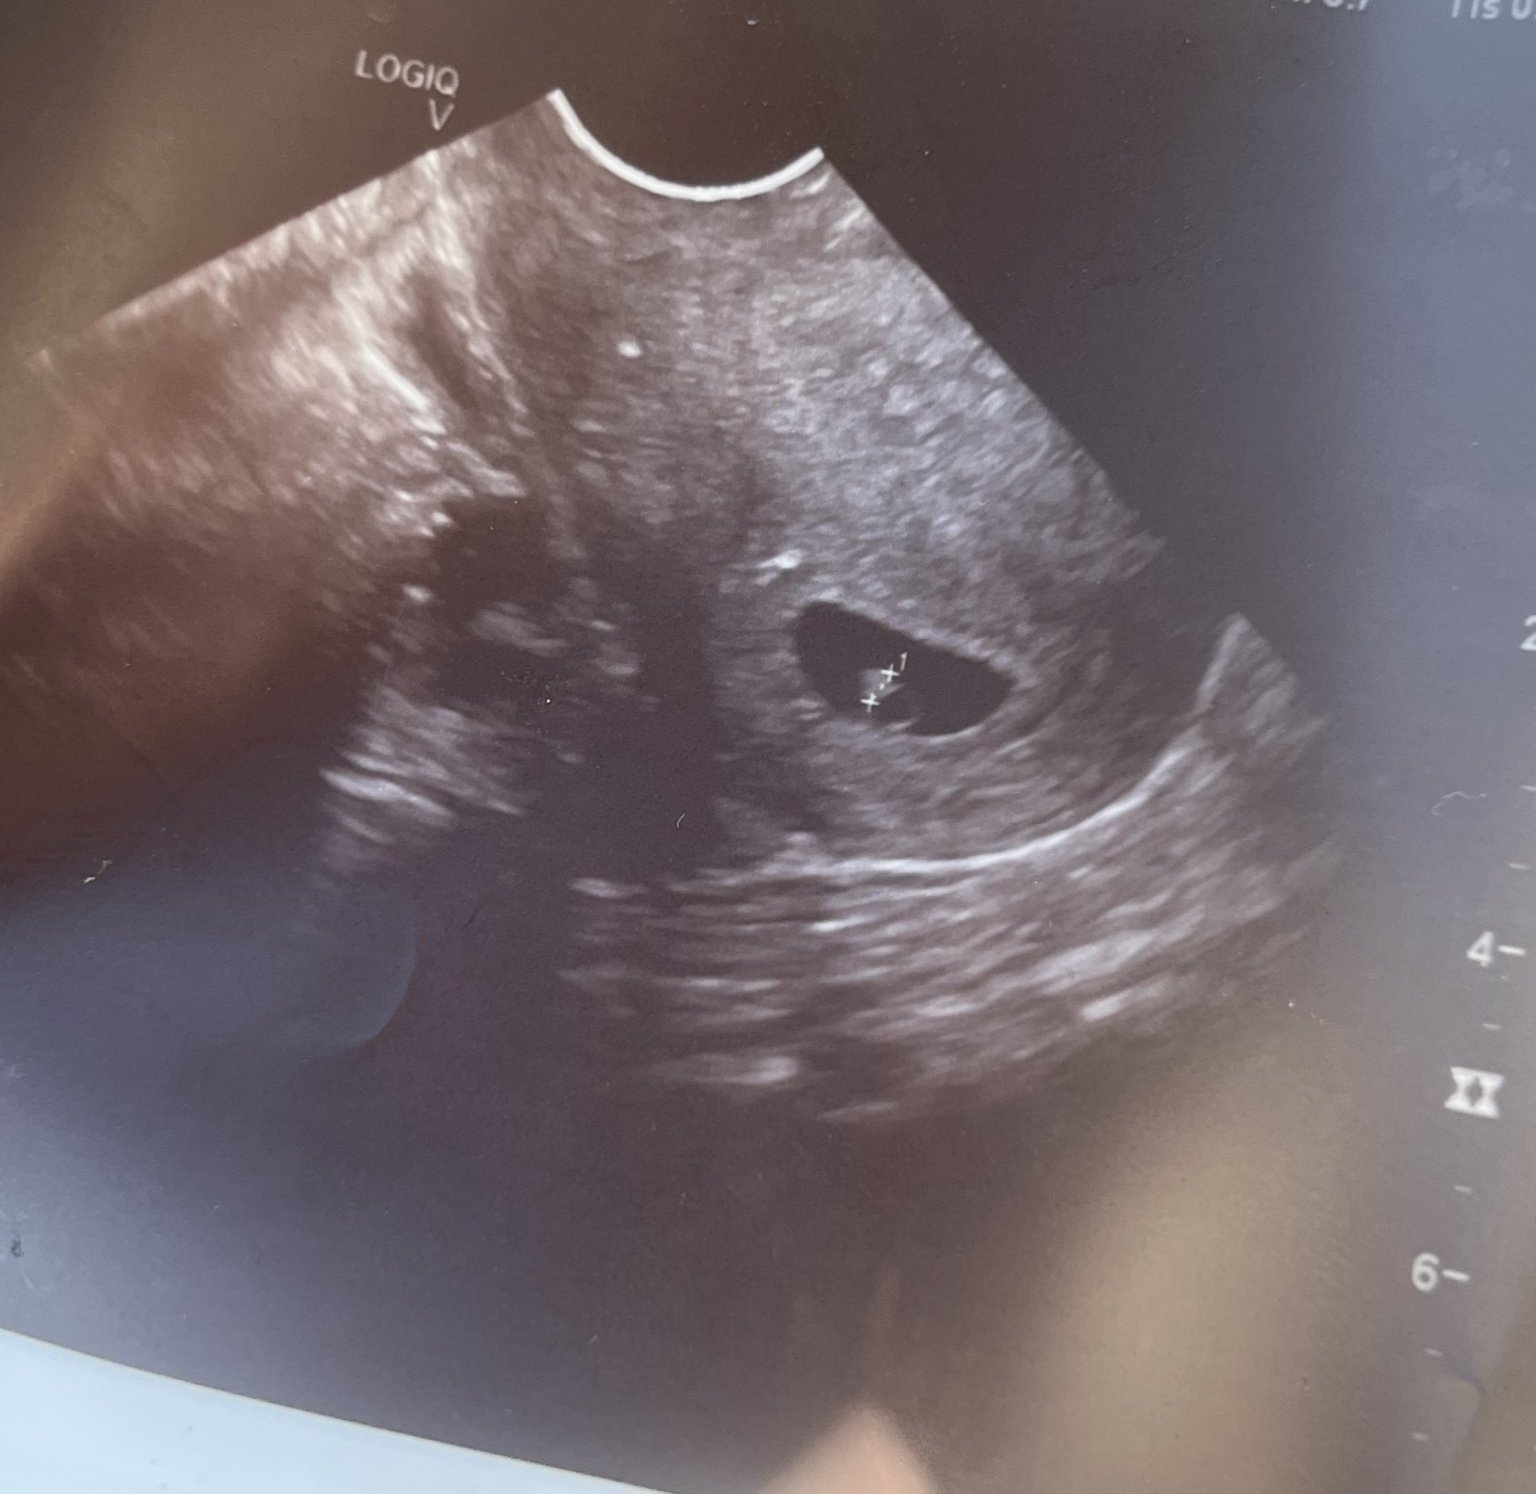

Какво представлява изображението от ехографията на 5-седмична и 2-дневна бременност?